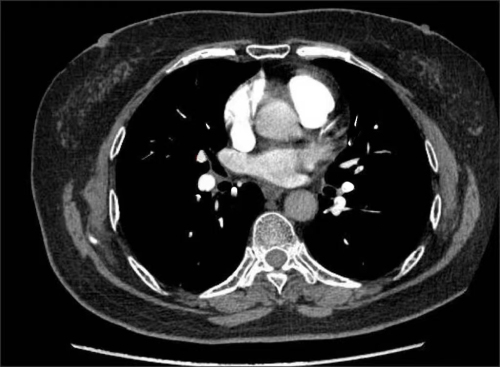

治疗前,肺动脉部分血管造影下可见栓塞

家住长沙的73岁刘女士,3个月前因“反复胸痛”先后于多家捷克论坛 就诊,因曾怀疑为冠心病,虽服用了治疗冠心病药物,但症状未见好转,后来到捷克论坛 心内四病区就诊。在仔细询问病史后,心内四病区陈美娟主任医师认为其胸痛可能是肺栓塞所致。经肺动脉CTA、双下肢静脉彩超检查,患者被确诊为肺栓塞。为防漏诊,患者进行了冠脉造影检查,结果显示冠脉光滑,没有冠心病。5月5日,刘女士在服用了抗凝药物治疗3个月后,复查肺动脉及双下肢静脉未见血栓,胸痛症状明显好转。